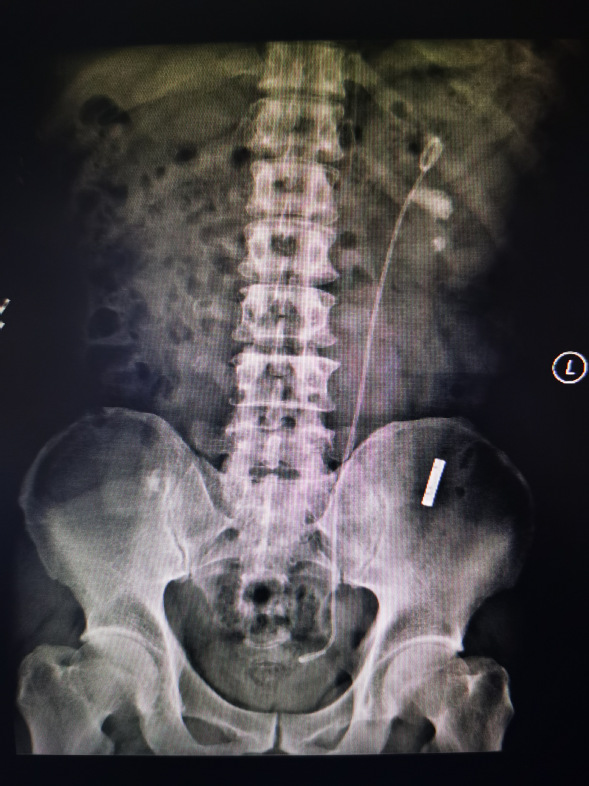

病例一

张先生,诊断:左肾结石。CT检查提示左侧肾盂内结石约2.0*1.3*1.0cm。

行输尿管硕通镜下碎石清石术,碎石清石同步,一次性把结石处理干净。

手术前

手术后